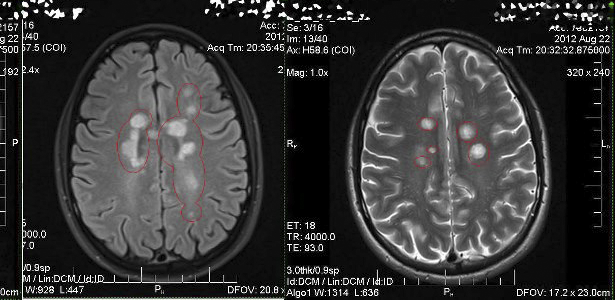

Ο αιματοεγκεφαλικός φραγμός είναι μέρος του τριχοειδούς συστήματος που αποτρέπει την είσοδο των Τ κυττάρων εντός του κεντρικού νευρικού συστήματος. Μπορεί να γίνει διαπερατός σε αυτούς τους τύπους των κυττάρων, δευτεροπαθώς, σε μια μόλυνση από έναν ιό ή βακτήριο. Τα Τ κύτταρα μπορούν να παραμείνουν παγιδευμένα στο εσωτερικό του εγκεφάλου. Η MRI-Magnetic Resonance Imaging-Απεικόνιση μαγνητικού συντονισμού αναδεικνύει τις βλάβες.

Τα συνηθέστερα χρησιμοποιούμενα διαγνωστικά εργαλεία είναι η νευροαπεικόνιση, η ανάλυση του εγκεφαλονωτιαίου υγρού (ΟΣΠ) και τα προκλητά δυναμικά. Η απεικόνιση μαγνητικού συντονισμού του εγκεφάλου και της σπονδυλικής στήλης μπορεί να δείξουν περιοχές απομυελίνωσης (αλλοιώσεις ή πλάκες). Γαδολίνιο μπορεί να χορηγηθεί ενδοφλεβίως ως σκιαγραφικό μέσο για να τονίσει τις πλάκες (καλύτερα να μη γίνεται). Η ΟΣΠ παρακέντηση μπορεί να παρέχει αποδεικτικά στοιχεία της χρόνιας φλεγμονής στο κεντρικό νευρικό σύστημα. Το εγκεφαλονωτιαίο υγρό έχει δοκιμαστεί για ολιγοκλωνικές ζώνες της IgG με ηλεκτροφόρηση, που είναι δείκτες φλεγμονής και ανευρίσκονται σε 75-85 % των ατόμων με ΣΚΠ. Η διέγερση του οπτικού νεύρου και των αισθητήριων νεύρων μπορεί να εξεταστεί χρησιμοποιώντας οπτικά και αισθητικά προκλητά δυναμικά.